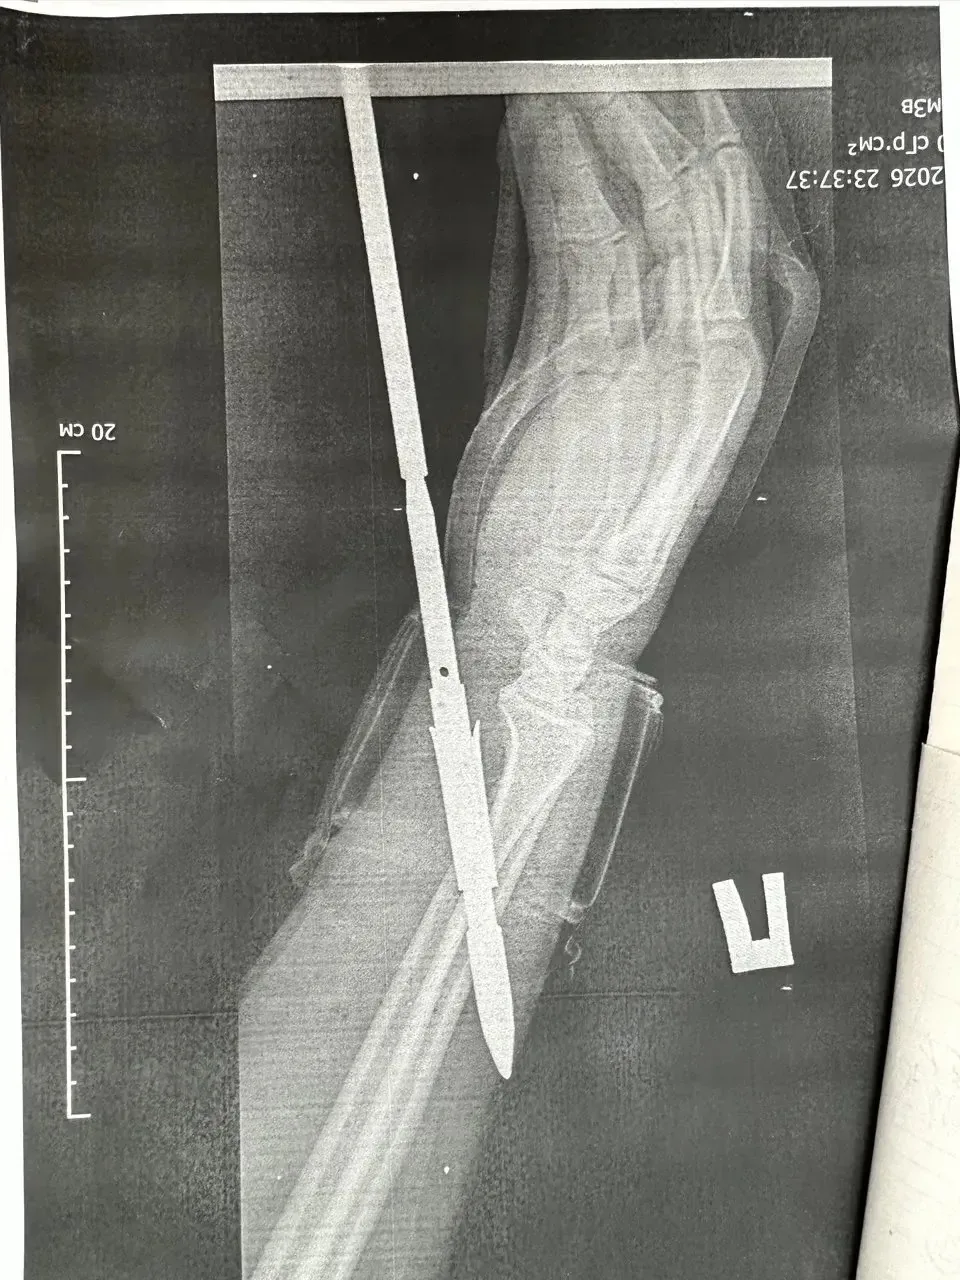

В отделение травматологии и ортопедии ГБ Орска поступил 29-летний мужчина, который загарпунил себя во время подводной охоты в Гайском округе. Гарпун с двумя зубцами прошёл между костями, не задев их.

Врачи извлекли инородное тело, обработали рану и оказали помощь. Сейчас пациент в хирургическом стационаре.